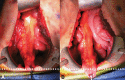

Ileal pouch-anal anastomosis allows for reestablishing gastrointestinal continuity in patients after proctocolectomy. The technical elements of pouch creation and gaining reach into the pelvis are demanding and require a variety of surgical maneuvers to achieve a tension-free anastomosis. We present a brief review of the literature discussing various approaches aimed at improving ileal pouch reach into the low pelvis. Although these techniques are used with different frequencies, they serve as important adjuncts to the gastrointestinal surgeons' armamentarium.